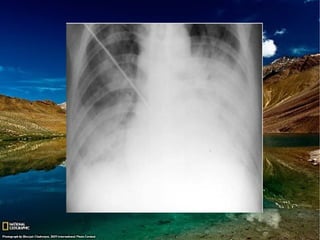

Achados de imagem

Radiografia de tórax:

Consolidação esparsa ou confluente uni ou

Afeta regiões pendentes dos pulmões;

Atelectasia(s);

Tomografia de tórax:

Opacidades em vidro fosco e consolidações

Opacidades centrolobulares mal definidas ou

Predomínio nas regiões pendentes dos pulmões;

Ocasionalmente pneumonia de aspiração pode estar